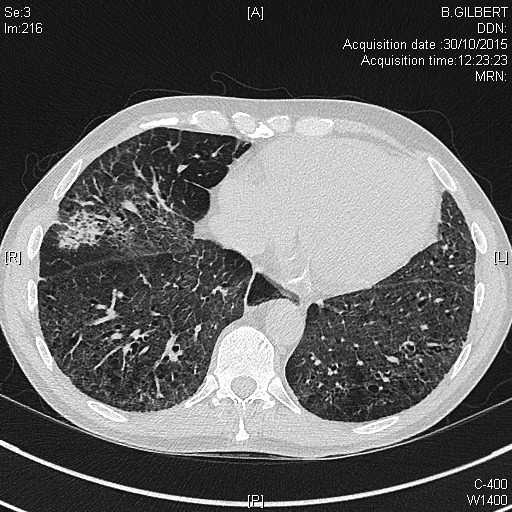

Pneumopathie interstitielle dans le cadre d'une myopathie inflammatoire à anticorps anti-MDA5